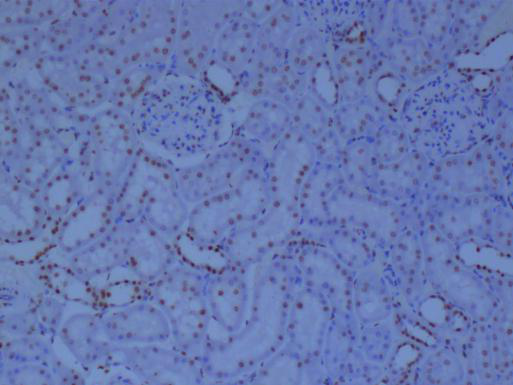

二、免疫組化:細胞與組織中的分子指紋

免疫組化技術(shù),則更多地被用于組織和切片水平的分析。通過特異性抗體與抗原的結(jié)合,結(jié)合顯色系統(tǒng),可以在組織切片上呈現(xiàn)出目標蛋白質(zhì)的表達情況,為疾病的診斷和病理學研究提供重要依據(jù)。

①高特異性:特異性抗體能夠精確識別目標蛋白質(zhì)。

②組織定位:能夠在組織切片上呈現(xiàn)目標蛋白質(zhì)的分布和表達情況,對于疾病的定位診斷具有重要意義。